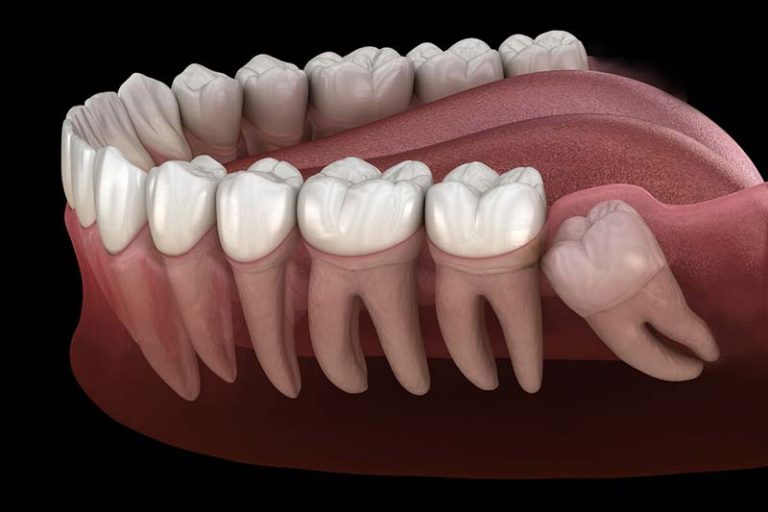

| رشد نادرست (دندان عقل نهفته) | دندان عقل نمیتواند به درستی بیرون بیاید و در زیر لثه یا استخوان باقی میماند. |

دندان عقل نهفته که به درستی رشد نمیکند: دندان عقل که در زیر لثه یا استخوان باقی میماند و نمی تواند به درستی بیرون بیاید، به عنوان دندان نهفته شناخته میشود. این وضعیت معمولاً نیاز به جراحی برای جلوگیری از عوارض بیشتر دارد.